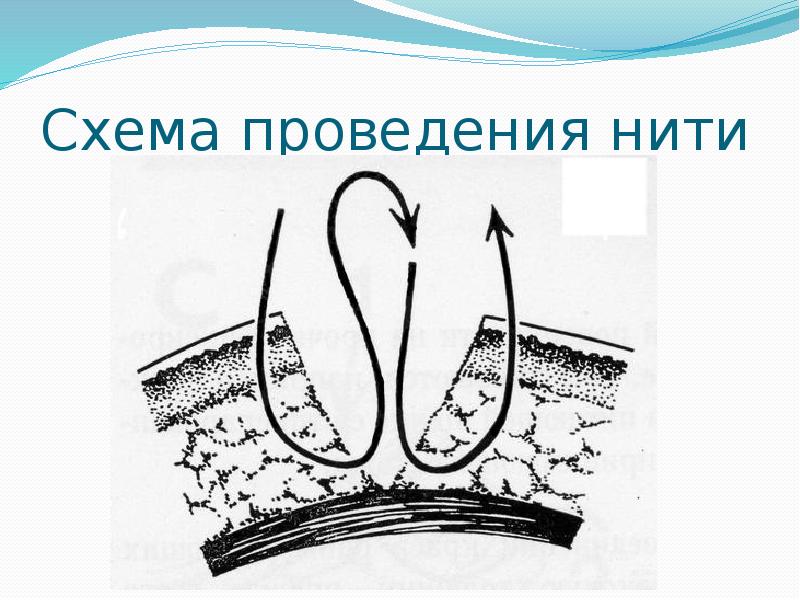

- 20. Схема проведения нити